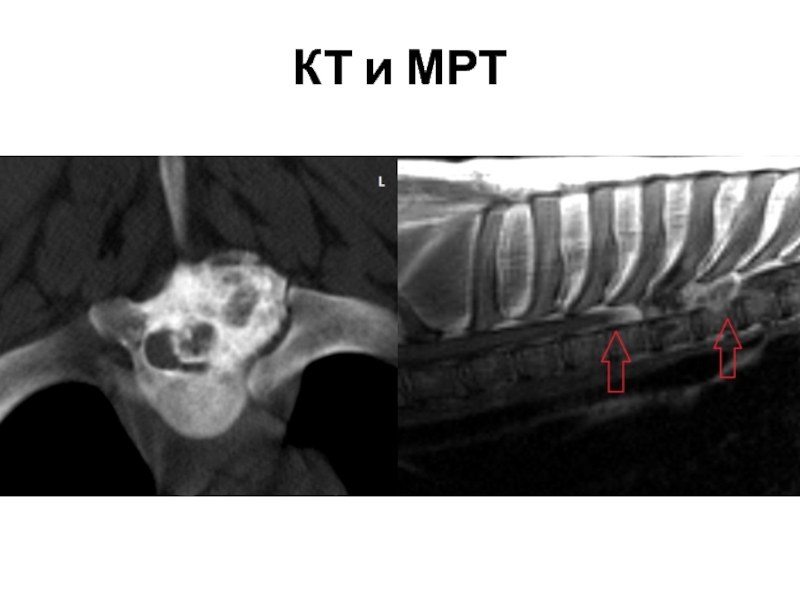

Компьютерная томография в неврологии презентация - 86 фото